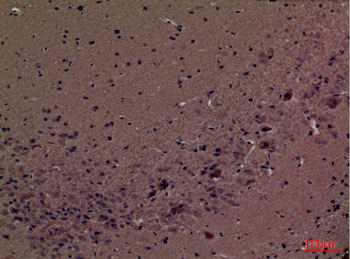

Anti-Cyclophilin A/PPIA Antibody [orb19174]

FC, ICC, IF, IHC, IHC-Fr, WB

Human, Mouse, Rat

Rabbit

Polyclonal

Unconjugated

10 μg, 100 μgCYPA Rabbit Polyclonal Antibody [orb100498]